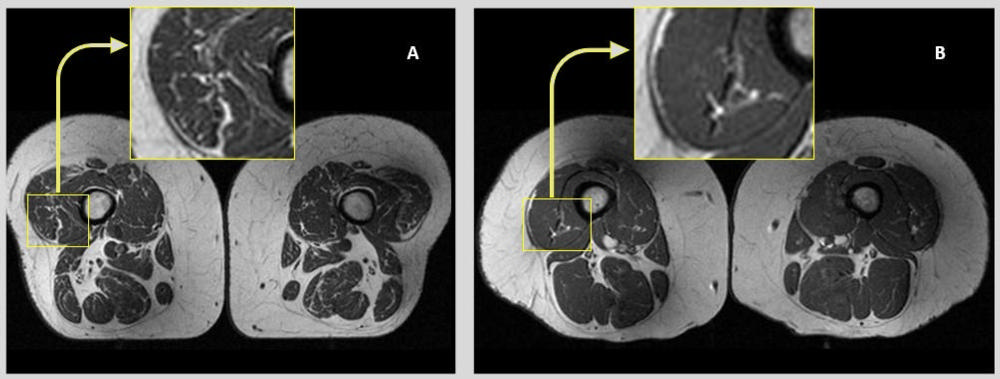

上图:不同饮食模式参与者的典型大腿 MRI 影像对比。UPF 摄入较高者的肌间脂肪信号更为明显。